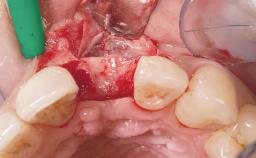

A 33-year-old female patient presented with an upper left central incisor that required extraction after a failed endodontic therapy. The tooth had been traumatized when the patient was a teenager and had undergone several endodontic treatments, including two apicectomy procedures. The patient was in good health and did not smoke. Clinical examination showed that the patient had a high lip line. In full smile, the gingival margins of the upper teeth were visible to the first molars. The gingival margins of central incisors 11 and 21 were only just showing. Examination of tooth 21 confirmed that the tooth was mobile and had hypererupted by 1 mm.

Placement Protocol Immediate implant placement

Socket Integrity Damage to one or more bone walls

Bone Volume Damage to one or more socket walls